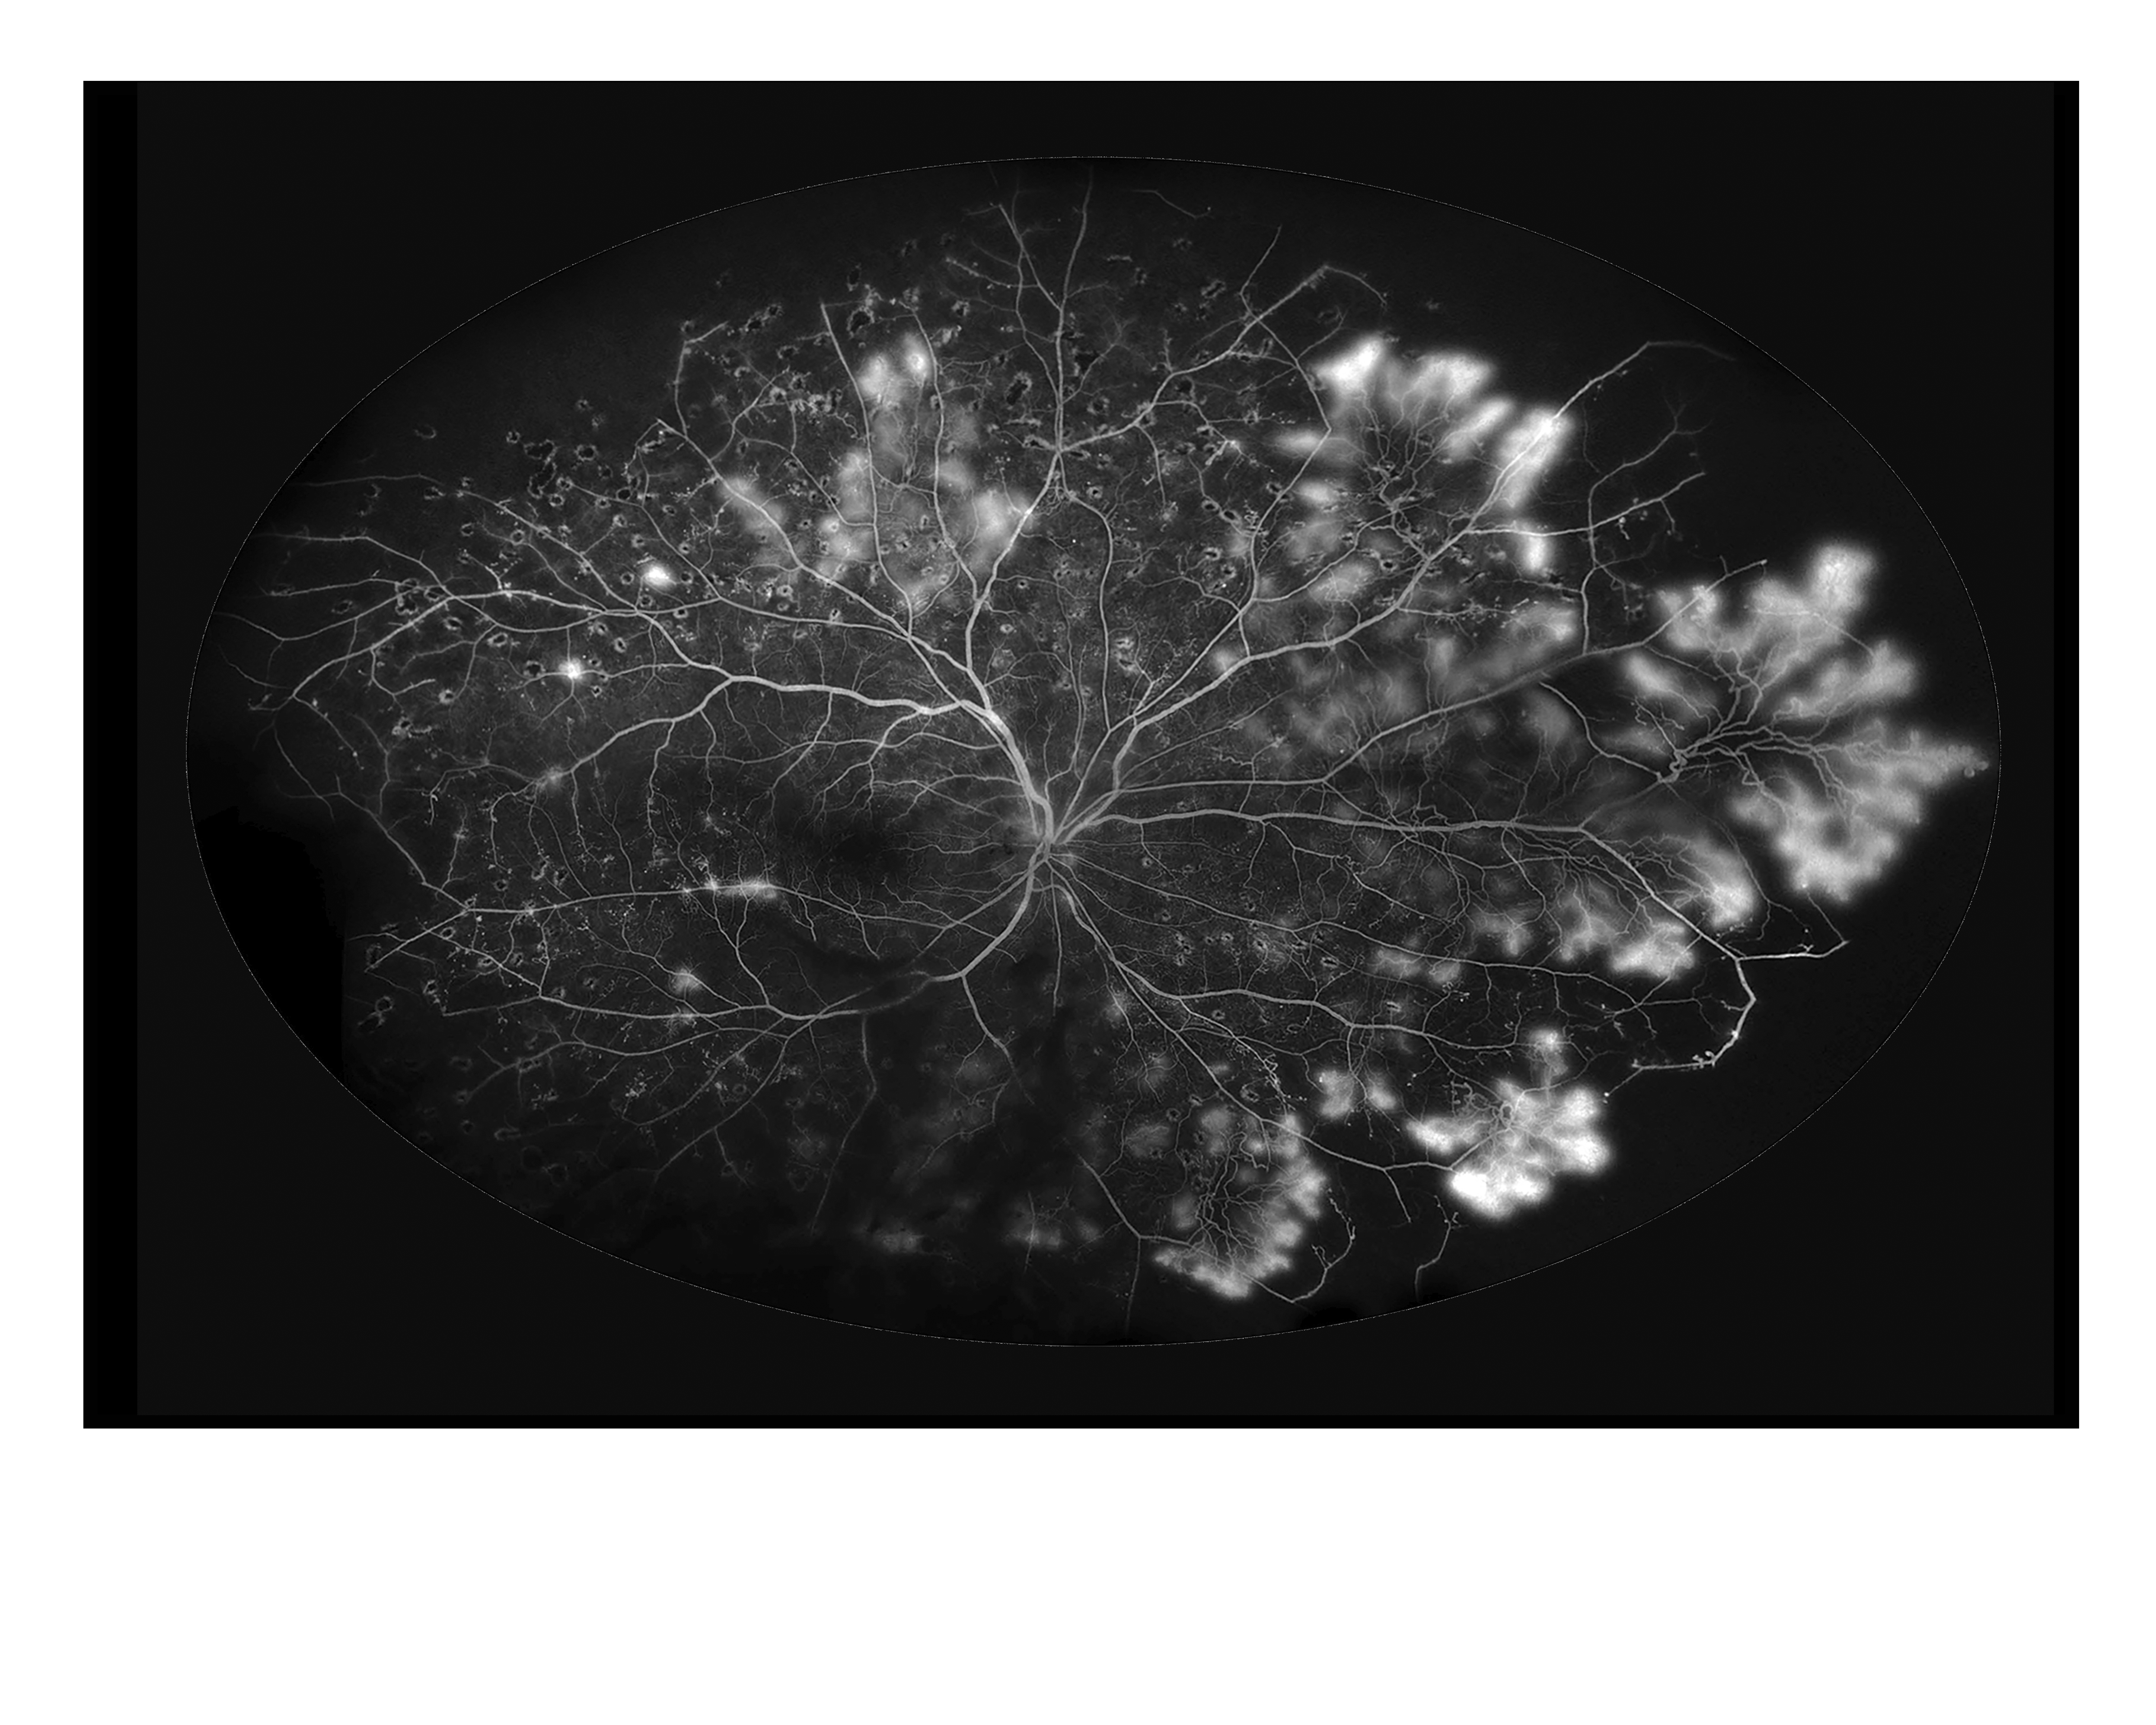

Sickle Cell Presented by Albert Alimpich This photograph received First Place in the category "Fluorescein Angiography" and was displayed in the 2024 OPS Exhibit. Filed Under Retina OPS Photo